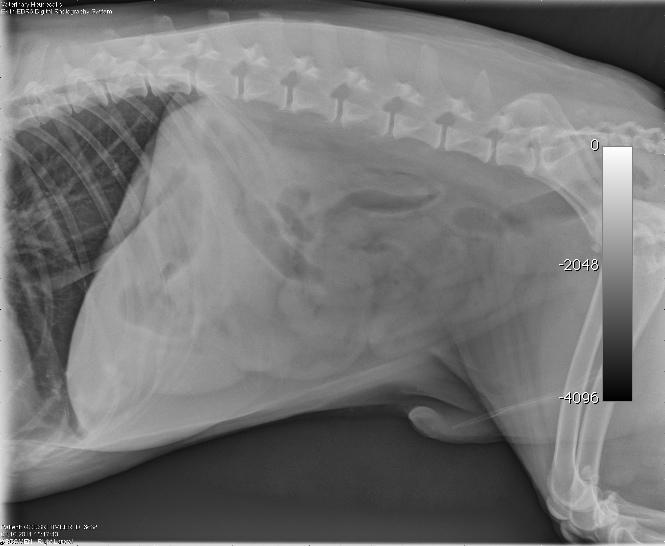

A 10 year-old MN Shepherd mixed dog presented with a 2-3 month history of intermittent vomiting and a more recent anorexia. Abnormalities on physical examination were dehydration and a 3 cm firm left anal sac mass. The only significant finding on CBC and serum biochemistry was hypoalbuminemia. Survey radiographs showed no evidence of pulmonary metastases but revealed excessive pyloric gas pattern with a volume contracted heart.